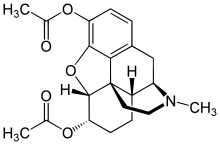

3,6-diesters of morphine

- Acetylpropionylmorphine

- 3,6-Dibutanoylmorphine

- Diacetyldihydromorphine (dihydroheroin, acetylmorphinol)

- Dibutyrylmorphine

- Dibenzoylmorphine (first designer drug)

- Diformylmorphine

- Dipropanoylmorphine

- Heroin (diacetylmorphine)

- Nicomorphine

Structures

| 3,6-diesters of morphine | ||||

|---|---|---|---|---|

Acetylpropionylmorphine Acetylpropionylmorphine |

3,6-Dibutanoylmorphine |  Diacetyldihydromorphine Diacetyldihydromorphine(dihydroheroin, acetylmorphinol) | ||

Dibutyrylmorphine Dibutyrylmorphine |

Dibenzoylmorphine Dibenzoylmorphine |

Diformylmorphine Diformylmorphine | ||

Dipropanoylmorphine Dipropanoylmorphine |

Heroin Heroin(diacetylmorphine) |

Nicomorphine Nicomorphine | ||